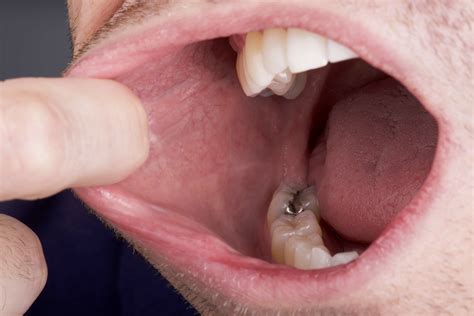

Diagnosis of Oral Skin Tags

Diagnosing oral skin tags typically involves a visual examination by a healthcare professional. In some cases, a biopsy may be performed to rule out other conditions, such as oral cancer. A biopsy involves removing a small sample of the tissue for laboratory analysis. This procedure is usually performed under local anesthesia and is generally painless.